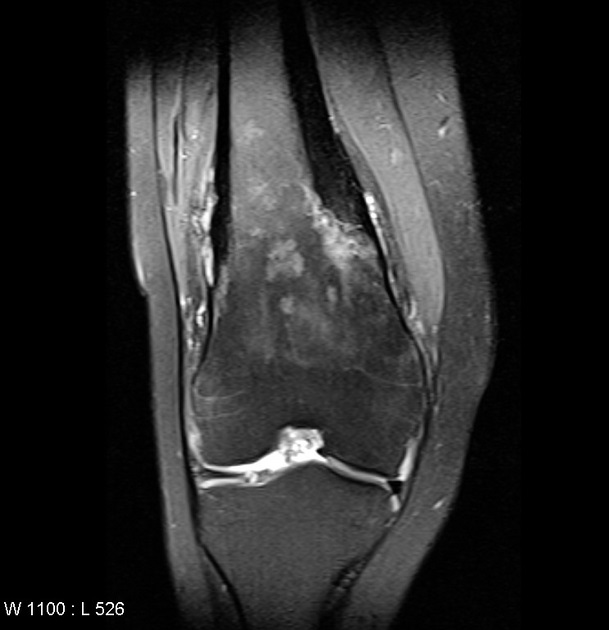

À os long la

lesion de syndrome de SAPHO est de osteolyse

et ostesclerose du diaphyse et à metaphyse des longs

os . Image radiologique IRM ponderee sur T1 en coupe

sagital

|

Même cas en coupe IRM frontal ponderee sur

T2 . Le syndrome de SAPHO se presence

souvent chez les adultes

jeunes ou d'âge moyen. Sa présentation dans la population

pédiatrique n'est pas rare ,les femmes > que les hommes

,

pathogénie inconnue

séronégatives

et affecter souvant sur

articulation sacro-iliaque , des os longs mais aussi encore à des

os de la paroi

thoracique antérosupérieure . Syndrome SAPHO est abrégé des

alfabetique suivant :

- S : Synoivite ,

- A : Acnee ,

- P : Pustulosis ,

- H : Hyperostose ,

- O : Osteite